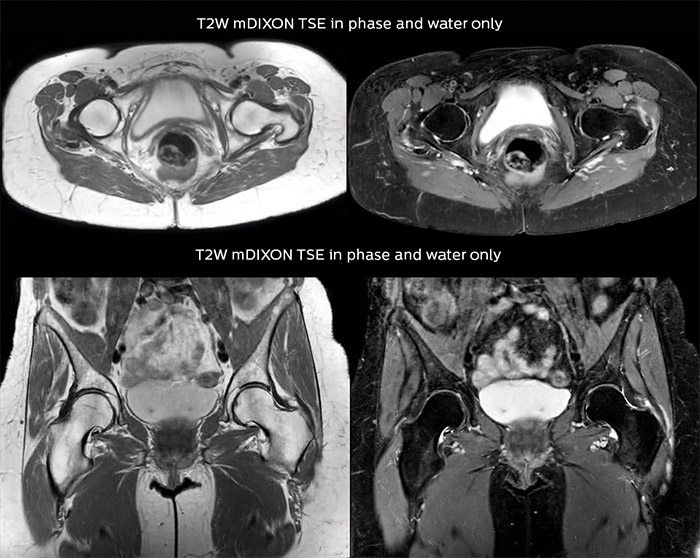

Bone assessment with confidence

“For bone assessment near joints, mDIXON TSE provides the visualization and multiple contrasts to describe abnormalities within a limited number of acquisitions. Bone marrow signal abnormalities are common MRI findings that can represent various underlying causes, from normal variance to malignancy. So, it is important for us to notice and characterize these findings. With different contrasts, both with and without fat signal as mDIXON TSE efficiently provides, we can make a confident diagnosis.”

“Other examples in bone are the signal description of a necrotic fragment in osteonecrosis, the signal description of tumoral matrix that has different components (necrosis, hemorrhage, cartilage, bone formation). These are all possible thanks to in-phase and water images from a single mDIXON acquisition.”

“In peripheral joints, mDIXON TSE imaging aids in diagnosing injuries in ligaments or tendons, for imaging degenerative and inflammatory pathologies such as osteoarthritis and rheumatologic disorders and for oncological exploration.”

“mDIXON TSE sequences allow simultaneous characterization of morphological changes from the in-phase T2-weighted images and visualization of edematous changes, thanks to the water T2-weighted images from the same acquisition. Anatomical and morphological considerations could be a partial or complete ligament tear, a bony avulsion or hematoma.”

“For soft tissue assessment mDIXON brings similar benefits. For example in one T2-weighted mDIXON TSE acquisition, having the multiple contrasts helps us assess abnormalities in peripheral nerves fascicles, which may be due to anatomical or inflammatory changes..”